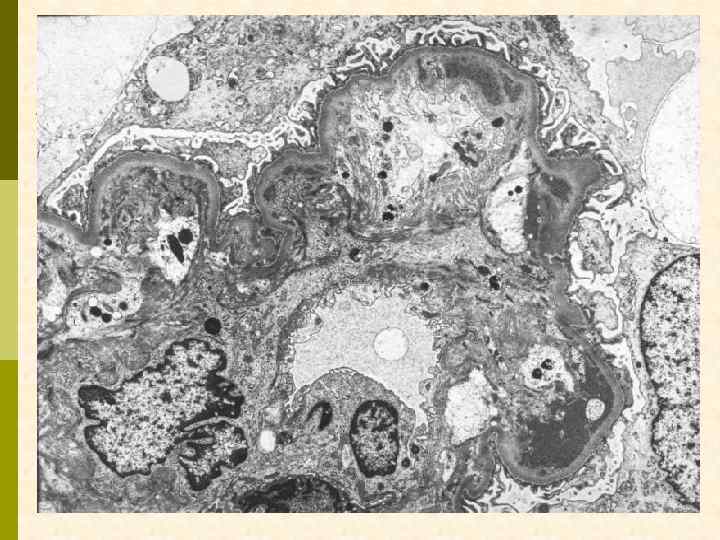

ВАРИАНТЫ ПЕРВИЧНОГО МЕМБРАНО-ПРОЛИФЕРАТИВНОГО ГЛОМЕРУЛОНЕФРИТА МПГН I типа МПГН II типа (DDD) (болезнь плотных депозитов с парциальной дистрофией) МПГН III типа (вариант Strife и Anders, вариант Burkholder)

Эритроцит МПГН, III тип. Грубые изменения ГБМ, резкое утолщение, лакуны, истончение плотной пластины, субэпителиальные депозиты

Гистологические варианты МПГН q Тип I – хроническая иммунокомплексная болезнь q иммунные депозиты в мезангии и субэндотелии q ассоциируется с гепатитом С, смешанной криоглобулинемией, гепатитом В, бактериальным эндокардитом q Тип II – болезнь плотных депозитов q С 3 при иммунофлуоресценции, но без иммуноглобулинов q аутоантитела к С 3 конвертирующему ферменту (C 3 Nef) q в 90% случаев рецидивирует в трансплантате q Тип III – хроническая иммунокомплексная болезнь q в отличие от I типа имеются субэпителиальные депозиты и разрушение базальной мембраны с прозрачными лакунами

МПГН-III (вариант Strife and Anders).